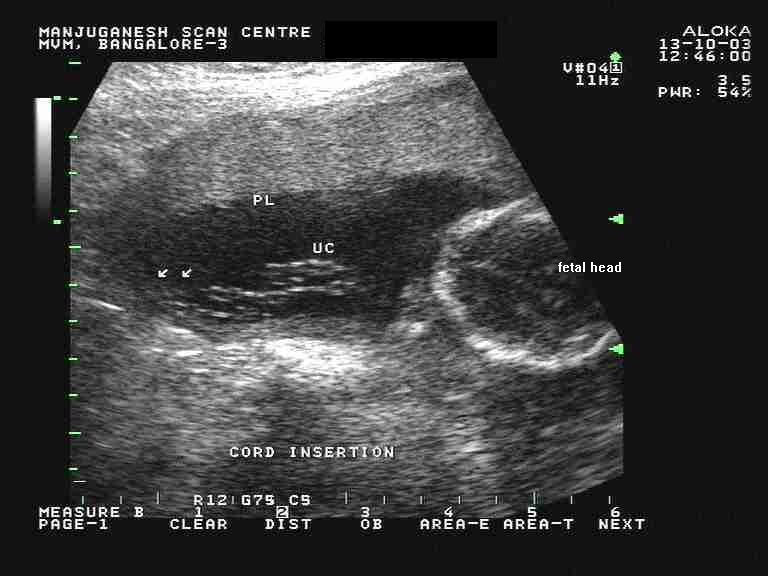

The placenta is on the posterior back uterine wall.

Mine was posterior and clear of the cervix so all is good with that. If the placenta attaches to the back of the uterus its known as a posterior. The placenta is that part that juts in making it more of a bean shape. See how were providing safe in person care and virtual visits.

Objectives we sought to determine the normal sonographically measured placental thickness in millimeters at the secondtrimester scan 18 weeks to 22 weeks 6 days and determine whether the measure. If its forming on the left side youre most likely expecting a girl. The placenta is on the back wall of the uterus and it is 62cm from the cervix. The placenta attaches to the wall of your uterus and its position can be anywhere front back right or left.